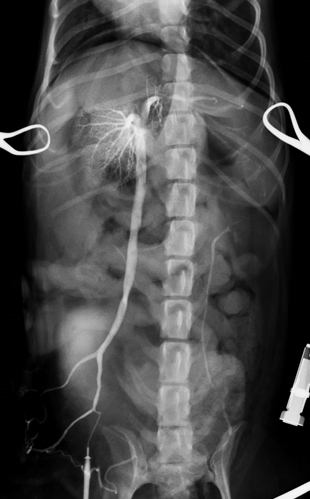

まず開腹下にて門脈造影検査と言われる特殊な血管造影検査を行い、シャント血管とレントゲン検査にて探します。今回検査にてシャント血管が左胃静脈-左横隔膜静脈を介した門脈-後大静脈シャントであることが判明しました。

左胃静脈-左横隔膜静脈を介した門脈-後大静脈シャント

実際のシャント血管です。